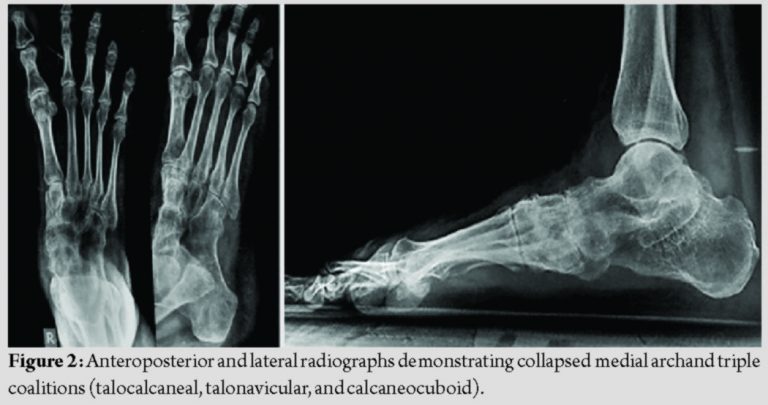

A 24-year-old female patient presented with complaints of painful deformity of her right foot with marked restriction of activities. Over the past 2years, she received conservative management in the form of medications, physiotherapy, and orthotics without any relief. Clinical examination revealed a planovalgoid foot along with a tight gastrocnemius, with a preserved ankle range of movements (Fig. 1). The subtalar and transverse tarsal joint movements were absent, along with tenderness over the subtalar, talonavicular, and calcaneocuboid joints. The diagnosis was confirmed with standing radiographs. Radiographs demonstrated the congenital fusion of subtalar, calcaneocuboid, and talonavicular joints with heel in valgus (Fig. 2).